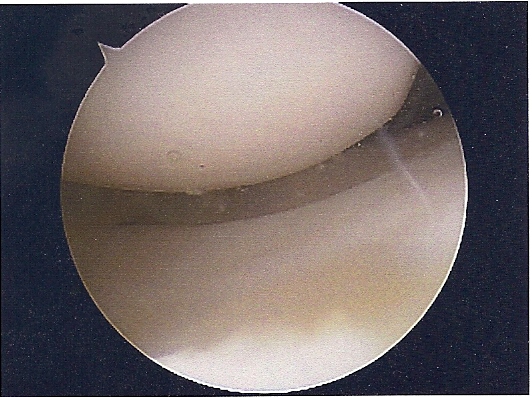

She had ACL replacement surgery on March 28th, using Bone-Patellar-Bone graft from her own patellar tendon. These are the images are scanned from pictures taken by the scope during the surgery. We were supposed to get a DVD of the procedure, but forgot to remind him on the day of the surgery. Oh well...

NEW ACL